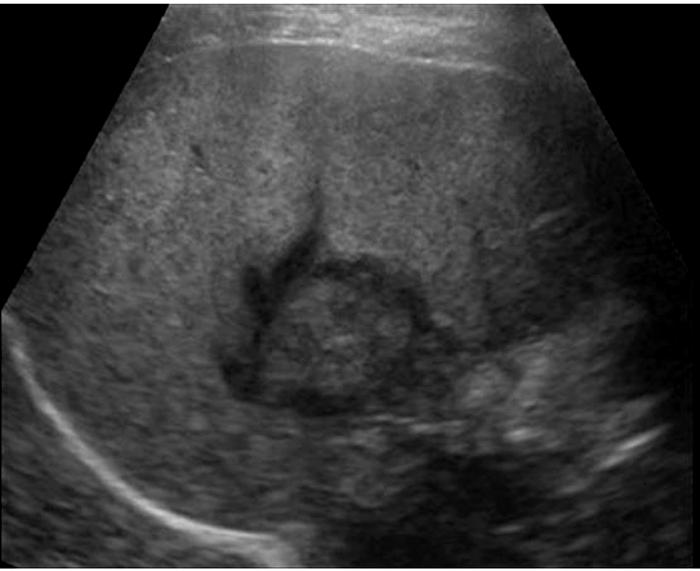

Caroli's Disease

congenital cystic dilatation of the intrahepatic biliary tree